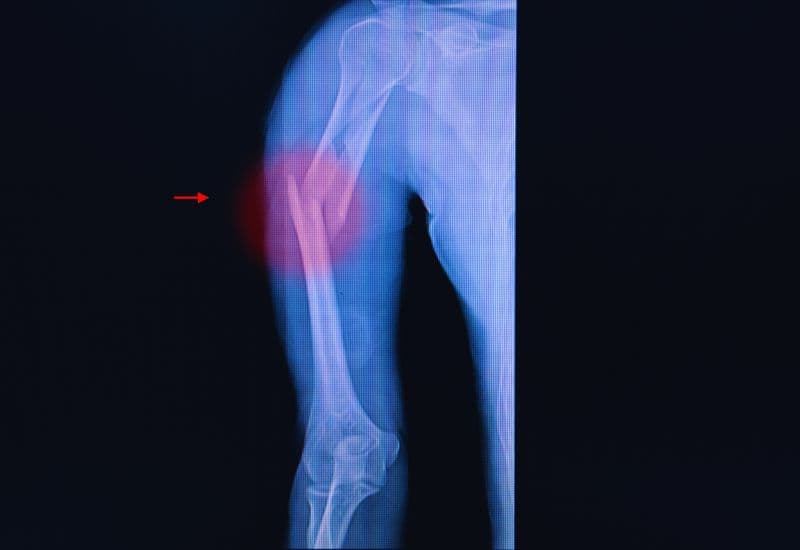

3.3 Biến dạng cánh tay

Khi xương cánh tay bị gãy, có thể nhìn thấy sự biến dạng hoặc lệch của cánh tay. Cánh tay có thể bị cong hoặc mất đi hình dáng bình thường, gây khó khăn trong việc di chuyển. Biến dạng này thường xuất hiện khi xương bị gãy thành nhiều mảnh hoặc gãy xương có di lệch nhiều.